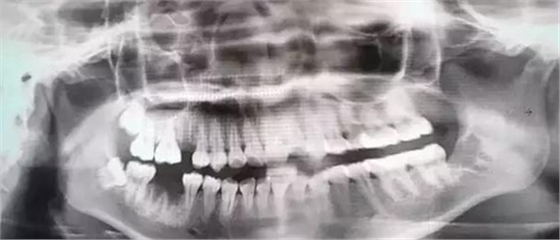

由于智齒的生長位置特殊,導(dǎo)致了拔除難易不同,如智齒出現(xiàn)橫著長或者靠近牙神經(jīng)的話,則難度會較高,一般人只需拍個口腔全景片,但相對于智齒靠近神經(jīng)管的情況,還可能需要拍CT,這都很考驗(yàn)牙醫(yī)的技術(shù)。

下面這兩張圖,據(jù)說拔牙費(fèi)時1.5小時,收費(fèi)14000元。